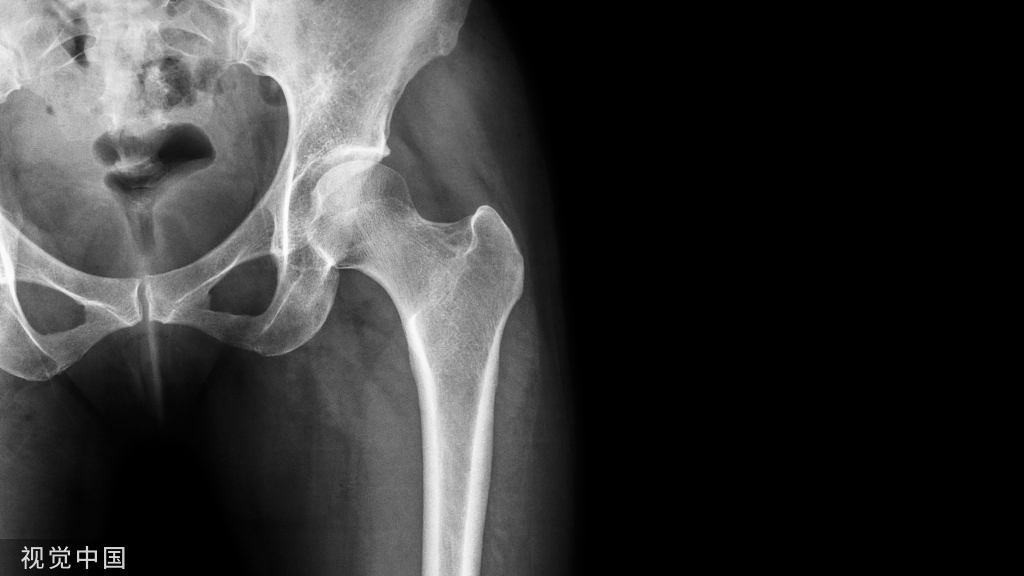

该图显示从上方观察臀大肌

髂嵴、股骨大转子和坐骨结节是臀区最基本的骨性标志。臀襞儿近水平位,大致与臀大肌下缘相一致、稍斜向下外侧。